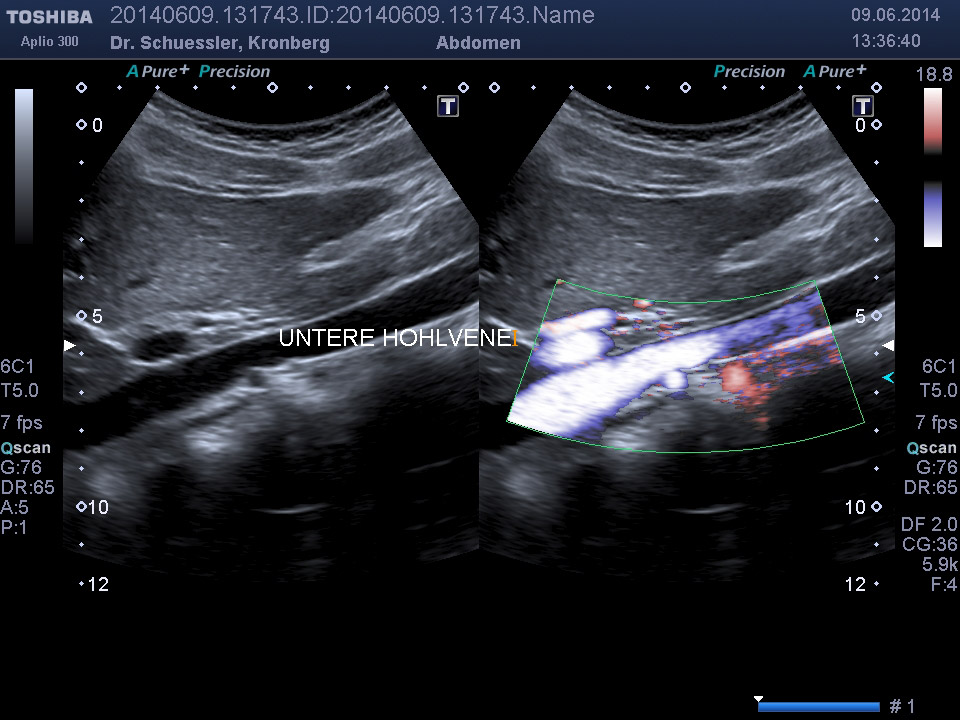

Durch Ergänzung des farbkodierten Duplexverfahrens läßt sich die Durchblutungssituation der Bauchorgane erfassen.